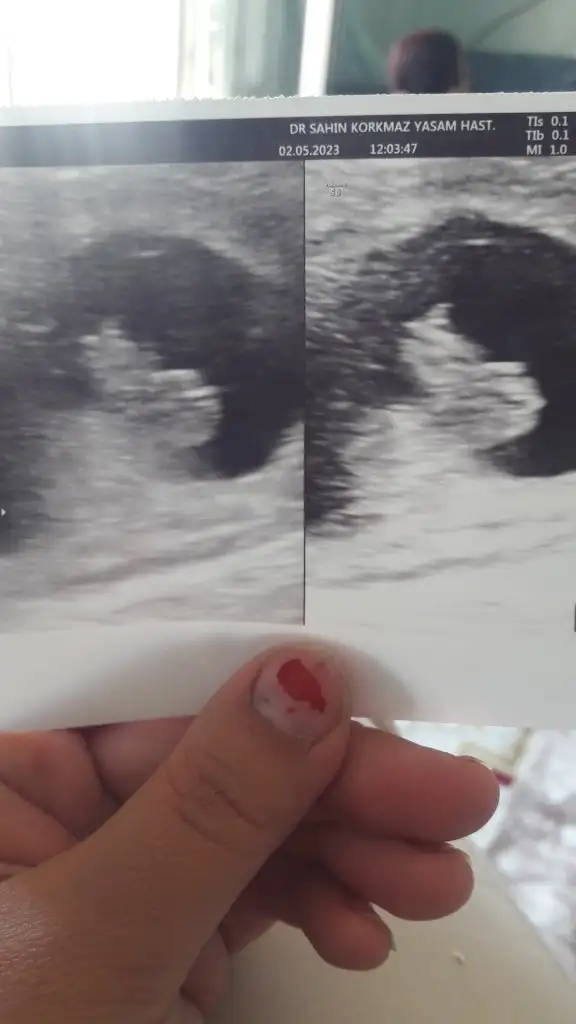

Bebeğimin cinsiyeti